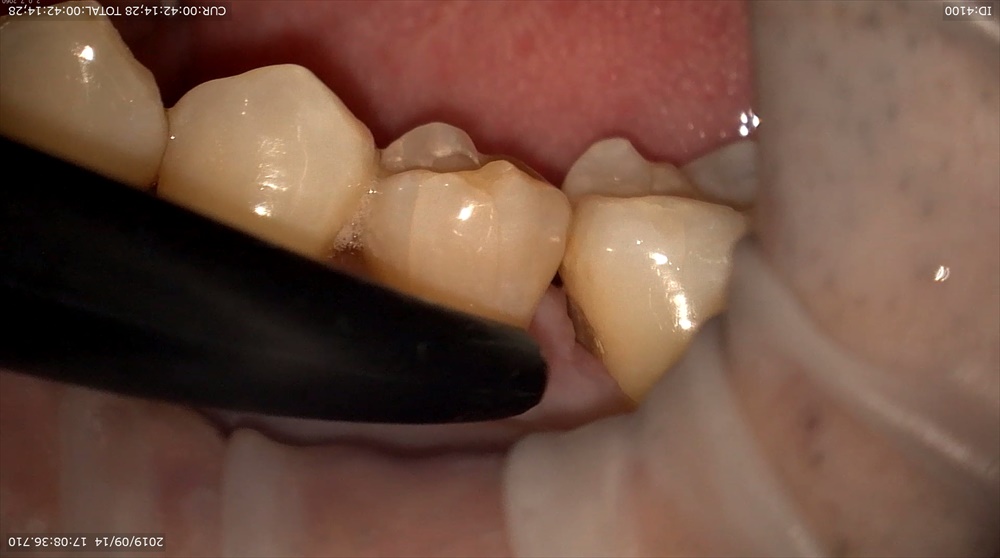

8倍率

3倍率では分かりにくかった黒点がこんなにも傷ついているのが分かると思います。